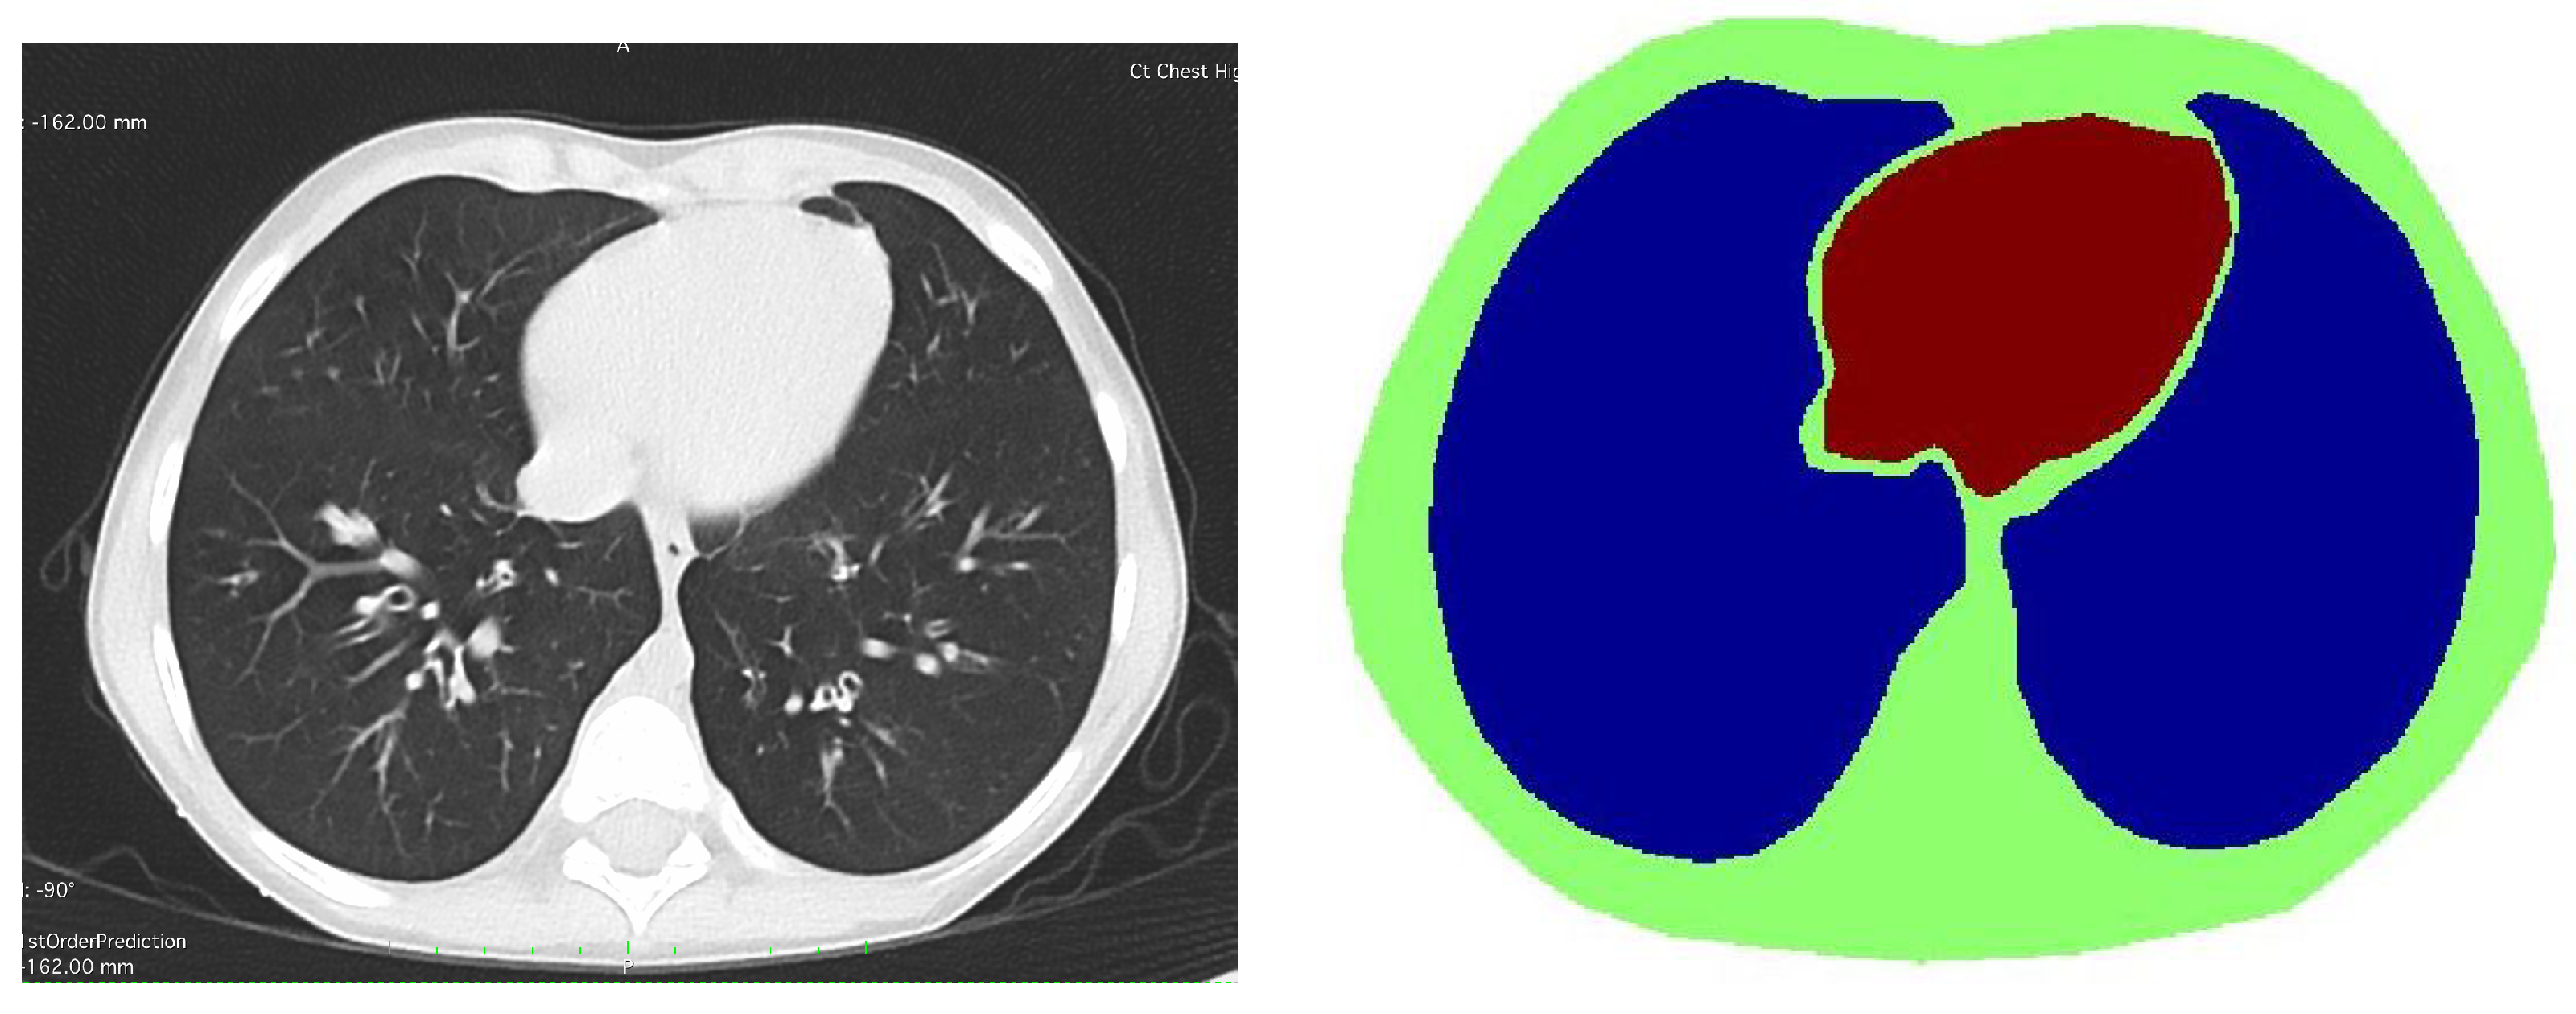

4.3. Human Subject Data